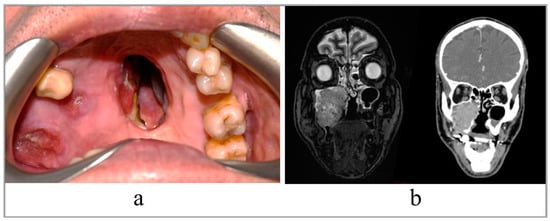

Figure 2. The steps for preparation of the AR guidance application for HoloLens 2 glasses (Redmond, WA, USA).

Anatomical areas of interest for the surgery were segmented using D2P™ software (3D Systems Inc., Rock Hill, SC, USA), a certified software package designed to convert DICOM medical images into 3D digital models. In detail, the maxillary bones, the tumoral mass in the midface region and the facial skin were segmented as separated masks from the CT scan. Then, three-dimensional polygonal surface meshes were generated from each segmented mask and saved in STL (Standard Tessellation Language) format.

Using a 3D modeling software (Meshmixer, Autodesk Inc., San Rafael, CA, USA) virtual planes for maxillary bone resections were planned following the indications of maxillofacial surgeons, and then converted in STL objects (Figure 3).

Figure 3. Virtual planes for maxillary bone resections.

The obtained virtual models of the anatomical parts and the planned resection planes were imported into Unity 3D (Unity Technologies, San Francisco, CA, USA), a software provided with a specific development kit for creating augmented reality applications (Vuforia Engine package, PTC, Inc., Boston, MA, USA).